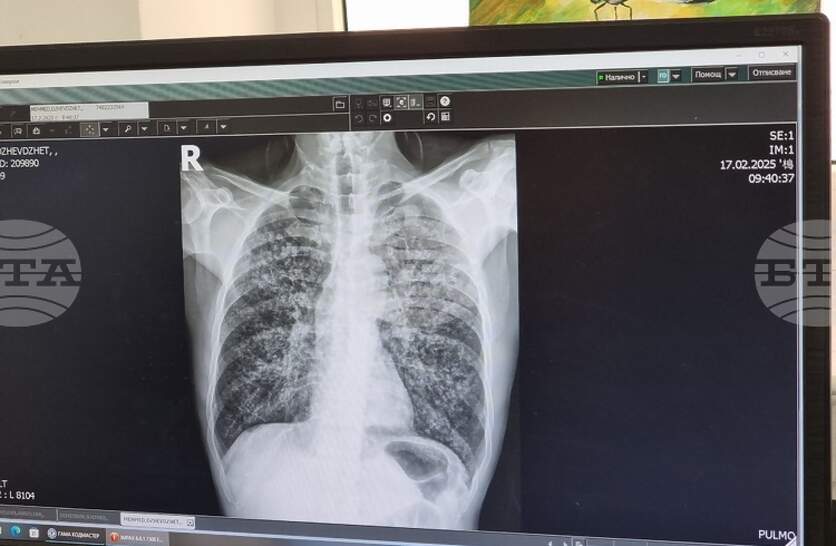

Плевенската университетска болница "Д-р Георги Странски" организира кампания за оценка на риска от белодробна туберкулоза. За това съобщават от лечебното заведение на официалната си страница във Фейсбук. В дните от 8-и до 12 декември в отделението за диспансерно наблюдение на болни с пневмо-фтизиатрични заболявания ще извършват прегледи от 12:30 до 14:30 часа. Необходимо е предварително записване на място или на тел. 064/802 994 с цел по-добра организация на работата, допълват от болницата. Всички процедури във връзка с кампанията ще бъдат напълно безплатни за участниците, независимо от здравноосигурителния им статут. Процедурата включва попълване на анкети, медицински прегледи и консултации със специалисти. При необходимост медицинският екип ще извършва и допълнителни изследвания. Кампанията за безплатни прегледи за оценка на риска от туберкулоза се организира четири пъти годишно. Последната се състоя през септември.